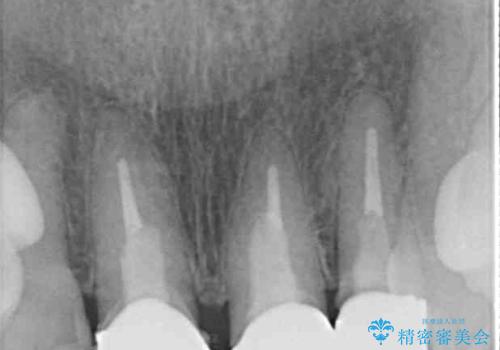

- 黄色みのある前歯のセラミックを、明るい色に替えたいとのことで来院された患者様です。

透明感がないことも気になっていたため、オールセラミッククラウンでは透けてしまう可能性のある金属の土台をファイバーコアに置き換え、1トーン明るいクラウンにて仕上げていくこととしました。